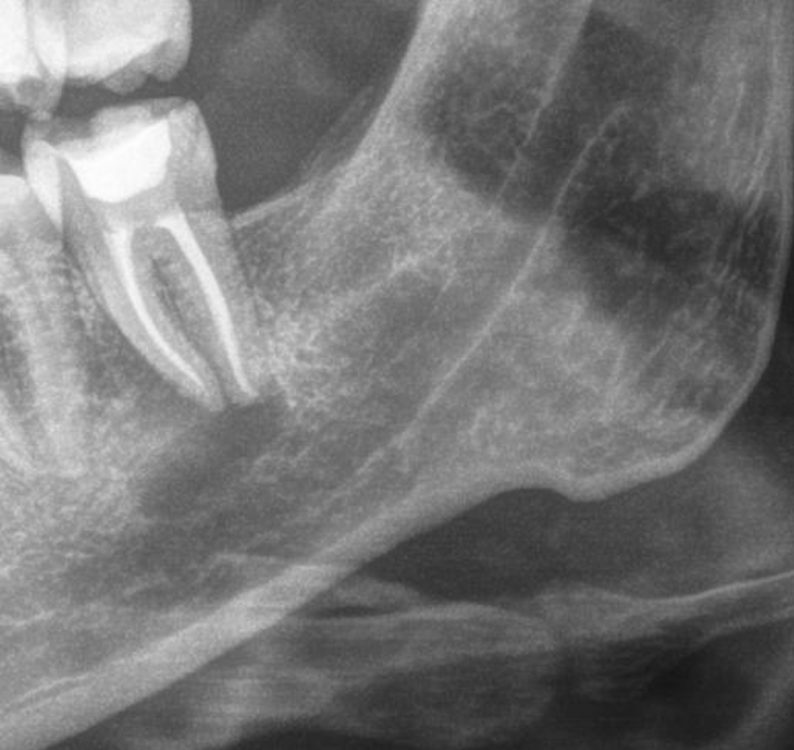

Начала ныть десна под депульпированной 10 лет назад нижней семеркой. Сделал панорамный снимок и под зубом штука похожая на кисту. Сходил на осмотр, на осмотре врач сказал что зуб слегка шатается, скорее всего у тебя под ним киста. Я показал снимок, врач сказал что да, это киста и посоветовал сделать КТ и сказал что нет проблем ее консервативно вылечить. (Распломбировать канал, положить лекарство и киста должна пойти на убыль). Но уже после НГ, сейчас все закрывается изза праздников.

Меня смущает форма кисты, она продолговатая, хотя по идее должна быть круглая. И темное пятно под кистой в челюсти (выделил красным). Или я непрвильно смотрю и киста это только то в зеленом кружочке?